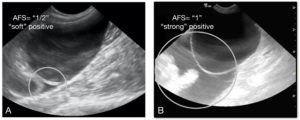

A visual showing you how the pocket to the left is a “1/2” and the pocket to the right a full “1” when assessing AFS at each of the 4 AFAST views.Copyright 2018 Gregory Lisciandro, DVM, Dipl. ABVP, ACVECC and FASTVet.com.

The under and over maximum dimension rule for the modification of the AFS. In cats < 5 mm is an AFS of “1/2” and > 5 mm an AFS of “1” and for dogs < 1 cm for “1/2” and > 1 cm for “1” with the 4 views being totaled as previously published. Copyright 2018 Gregory Lisciandro, DVM, Dipl. ABVP, ACVECC and FASTVet.com with Figures by Hannah Hey, San Antonio, Texas.